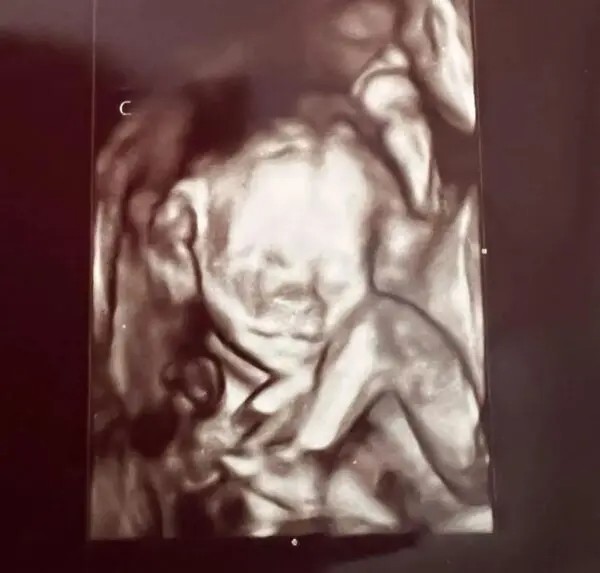

When Ashley had an ultrasound two weeks later and learned that she was expecting not one, but four babies, her joy quickly turned to shock.

The fact that the expecting woman, who already has a daughter from a previous relationship, learned that the four kids are actually two sets of identical twins rather than quadruplets astonished even her ultrasound technician.

When she got back, the doctor confirmed that Ashley is actually expecting four children, two boys and two girls.